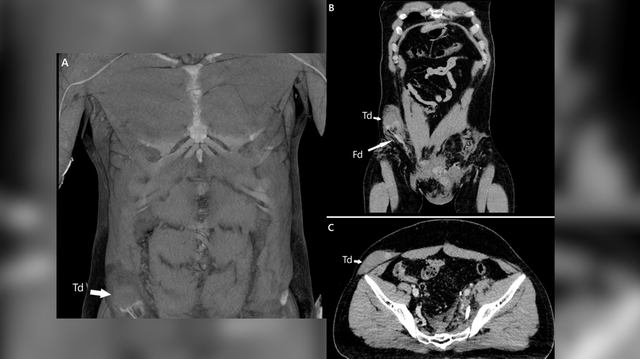

Namun, setelah dipindai menggunakan pemindaian tomografi komputer (CT), dokter menemukan testis pria itu mengalami masalah lebih serius. Testisnya masuk ke dalam perut dan harus dipindahkan ke tempat semestinya.

Testis kanan pria itu keluar dari skrotumโkantung kulit tipis yang menampung dua testis di bagian luar tubuhโ dan terdorong ke perut melalui saluran kecil di selangkangan setelah mengalami benturan hebat akibat kecelakaan sepeda motor.